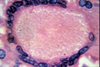

What is chronic cholecystitis?

Repeated damage and pain of the gall bladder due to obstruction of gall stones.

- Repeated acute inflammation leads to chronic inflammation

- Gall bladder wall becomes fibrosed